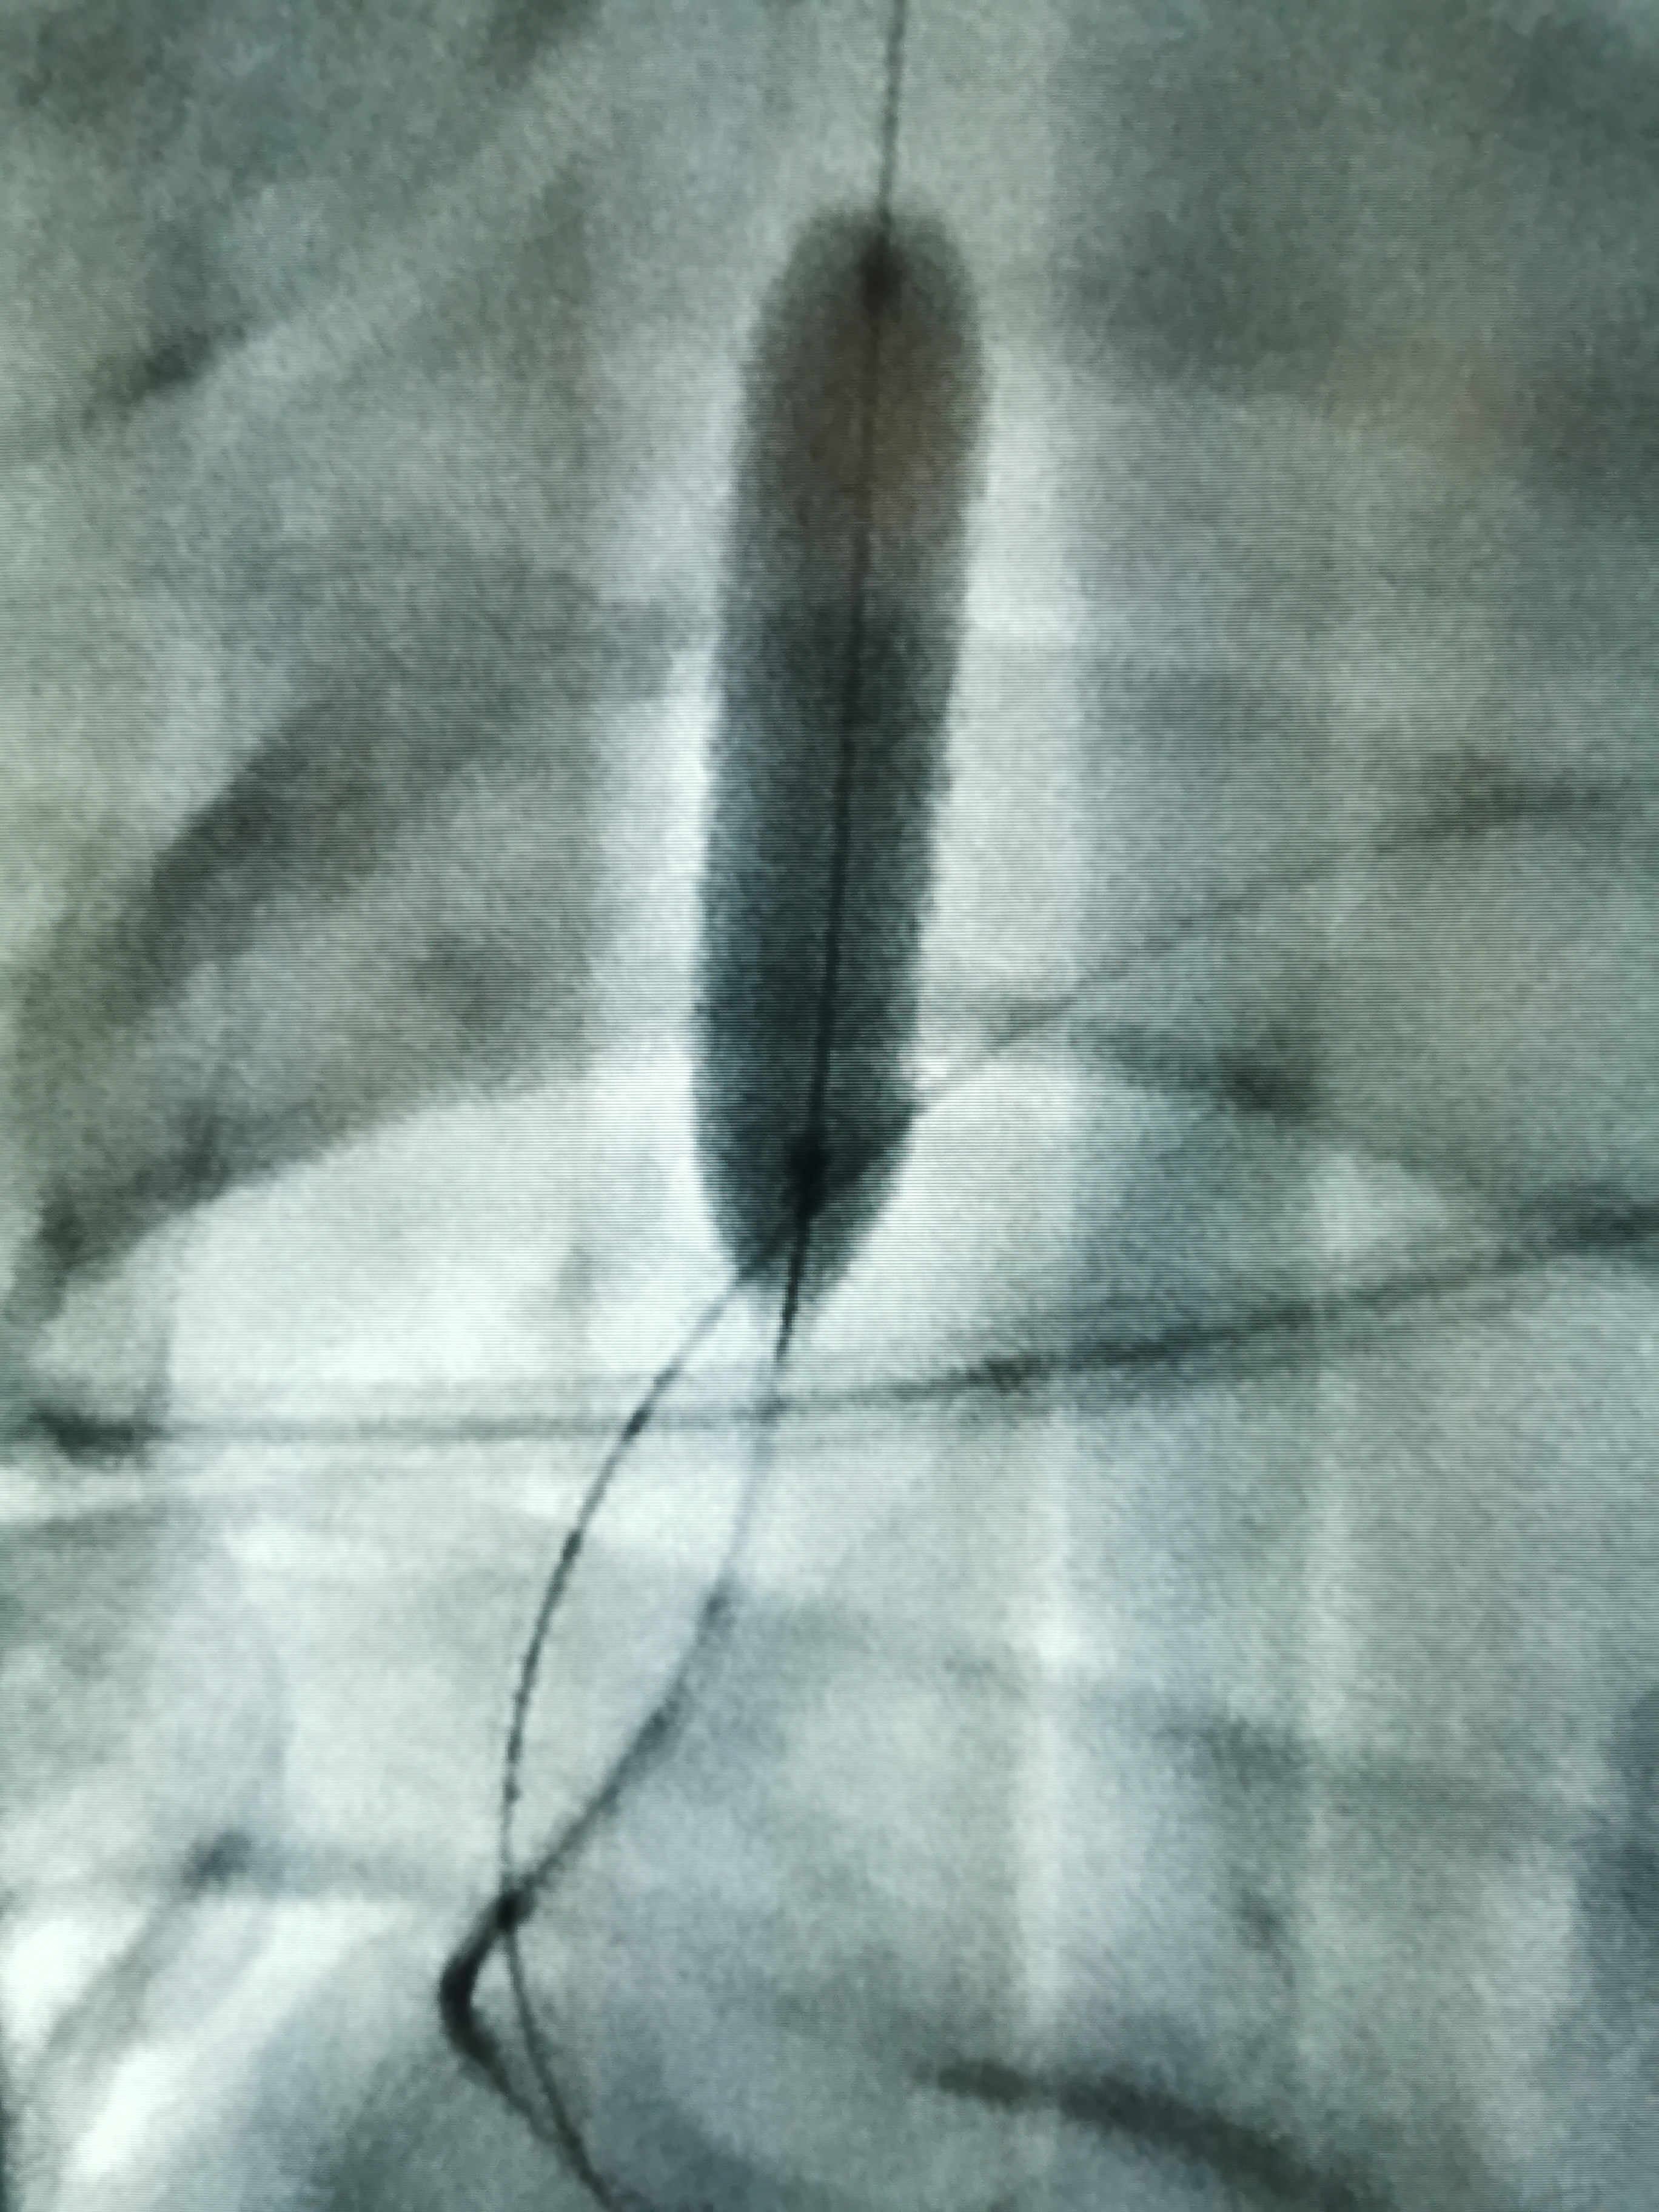

講話不清可以治療嗎?72歲老年男性,講話含糊不清伴反應(yīng)遲鈍9月余。老人家在口服抗血小板藥物、他汀藥物和控制高血壓、糖尿病的過程中,近9個(gè)月來一直講話含糊不清,并呈越來越重的趨勢,反應(yīng)能力也不是很好,由于以前發(fā)生過腦梗塞,家人也就認(rèn)為可能是以前的腦梗塞留下的后遺癥,只能慢慢康復(fù)了……最近,兒子帶老人家過來復(fù)查,檢查發(fā)現(xiàn)右側(cè)椎動脈起始部的狹窄越來越重,和9個(gè)月前相比,簡直判若兩人(管),左側(cè)椎動脈又先天發(fā)育不好……,看來保守治療吃藥不太行,還得需要外科干預(yù)和家屬商量后,我們采用全球首款椎動脈專用藥物洗脫支架(Maurora)成功精準(zhǔn)切線位植入,消除了這個(gè)“卡脖子”的狹窄……術(shù)后隨訪結(jié)果:老人家說話口齒清晰了,思維反應(yīng)也快了……按照說明說的介紹,與裸支架相比,Maurora可以降低再狹窄率66/……